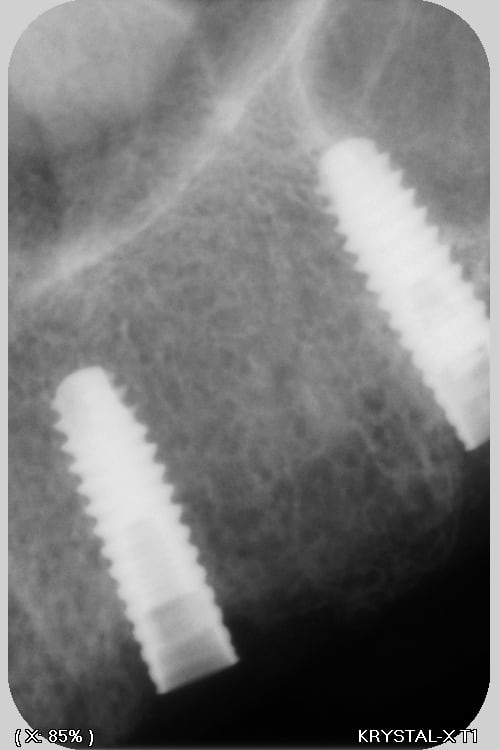

C'est de l'Anthogyr avec des piliers InLink

Il faut utiliser le tournevis Anthogyr pour accès angulé (tête boule)

Effectivement, c'est le seul truc que je n'utilise pas chez eux...c'est très ingénieux, mais dans le cas présenté, ils ont tous cassés..., j'attends de voir la prothèse d'origine pour savoir d'où vient le soucis.